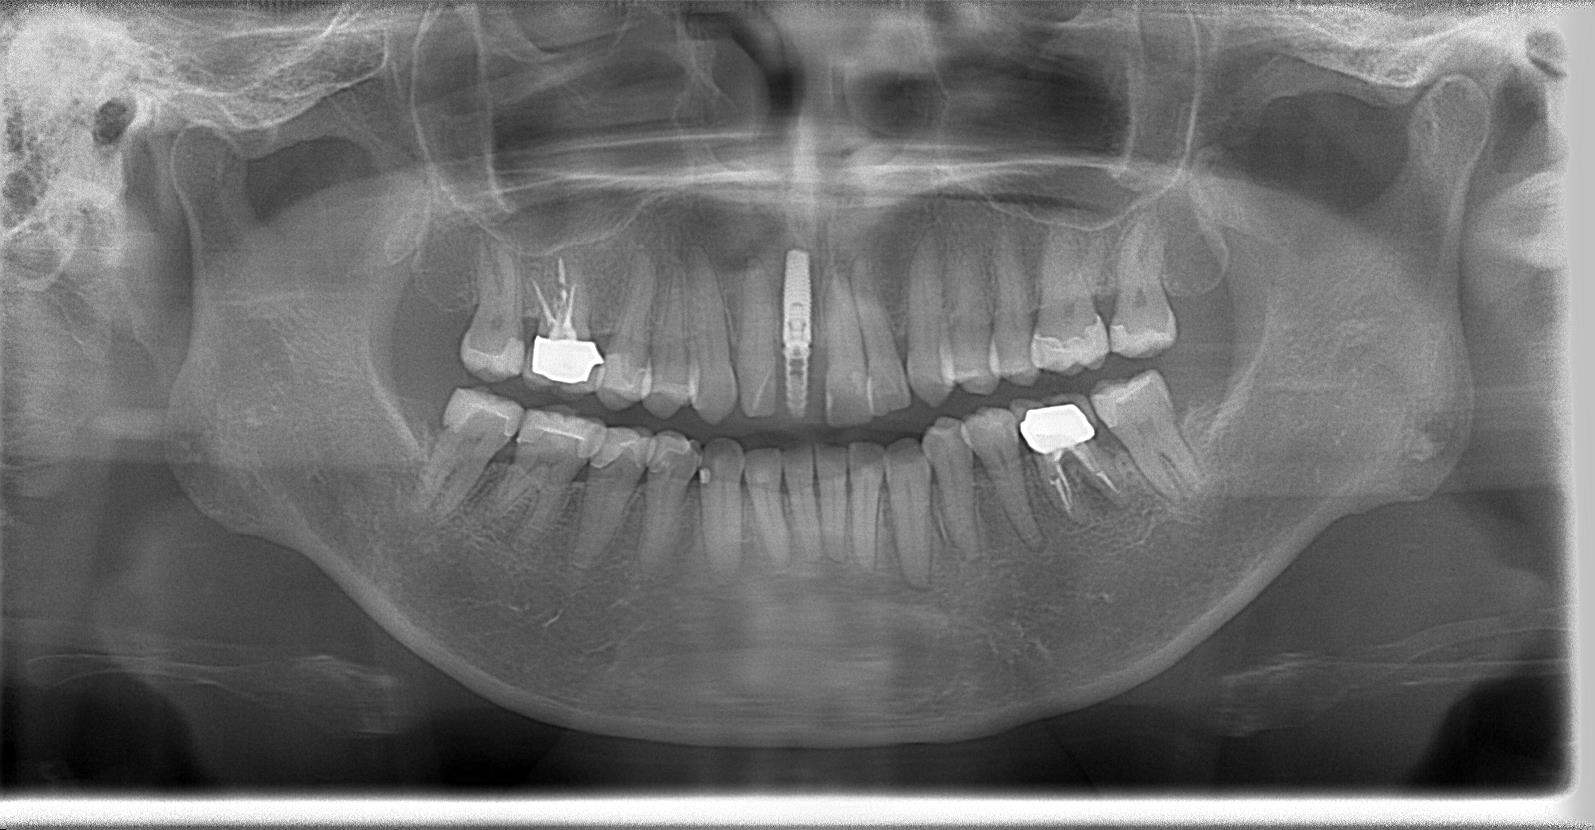

術後パノラマレントゲン写真